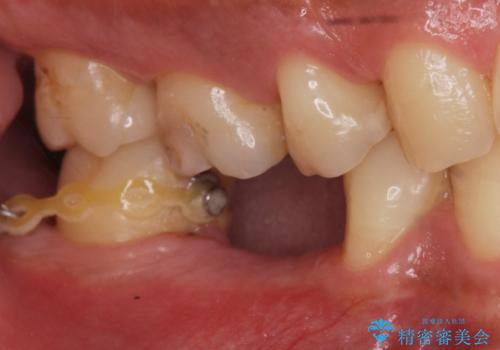

- 昔、治療された銀歯が気にな流ということを主訴で来院された患者様です。

銀歯を外し、虫歯治療を行い、セラミックインレーにて治療しました。

銀歯を除去し、虫歯をとって、セラミックインレーにて治療を行いました。